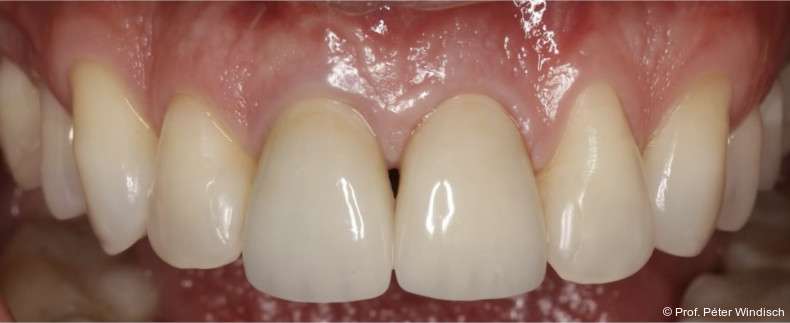

Das Emergenzprofil wurde mit einer polierten, eindeutig konvexen „S-Kurve“ neu gestaltet (Abb. 9+10). Diese neu entwickelte Geometrie schafft ausreichend Raum für die Weichgeweberegeneration, stützt den Gingivasaum, ohne durch überkonturierte („bulky“) Formen Nischen für Plaque zu schaffen. Die Synergie aus einer biokompatiblen Materialoberfläche (polierte Keramik) und einer reinigungsfähigen Anatomie stellt sicher, dass die Ergebnisse der submarginalen Instrumentierung dauerhaft stabil bleiben und der Patient die Stelle effektiv mit Interdentalbürsten pflegen kann.

Der Patient wurde angewiesen, zwei Stunden lang nichts zu essen oder zu trinken, sowie für die nächsten 24 Stunden keine Zahnreinigung oder CHX-haltige Mundspüllösungen und für die nächsten zwei Tage keine Interdentalbürsten zu verwenden.  Bei der Reevaluation nach sechs Monaten zeigte sich eine deutliche Verbesserung der periimplantären Gewebesituation. (Abb. 10+11). Durch die Behandlung konnten die klinischen Parameter deutlich verbessert werden. Die periimplantäre Sondierungstiefe wurde signifikant auf ein physiologische Taschentiefe reduziert, es war zudem keine Blutung auf Sondierung (BOP) mehr vorhanden.

Das Weichgewebe präsentierte sich klinisch entzündungsfrei. Radiologisch zeigte sich nach zwölf Monaten eine deutliche Verbesserung der knöchernen Situation im Sinne einer Auffüllung des knöchernen Defekts (Abb. 12). Das Ergebnis konnte durch regelmäßige Implantat-Maintenancetermine stabilisiert werden. Abbildung 13 zeigt die ausgereifte periimplantäre Hartgewebesituation.